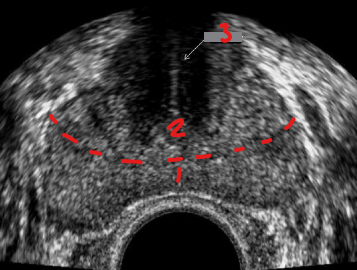

Identify this image.

Central zone

Peripheral zone

Transitional zone

Periurethral glandular zone

Verumontanum

Urethra

Ejaculatory duct

Fibromuscular region